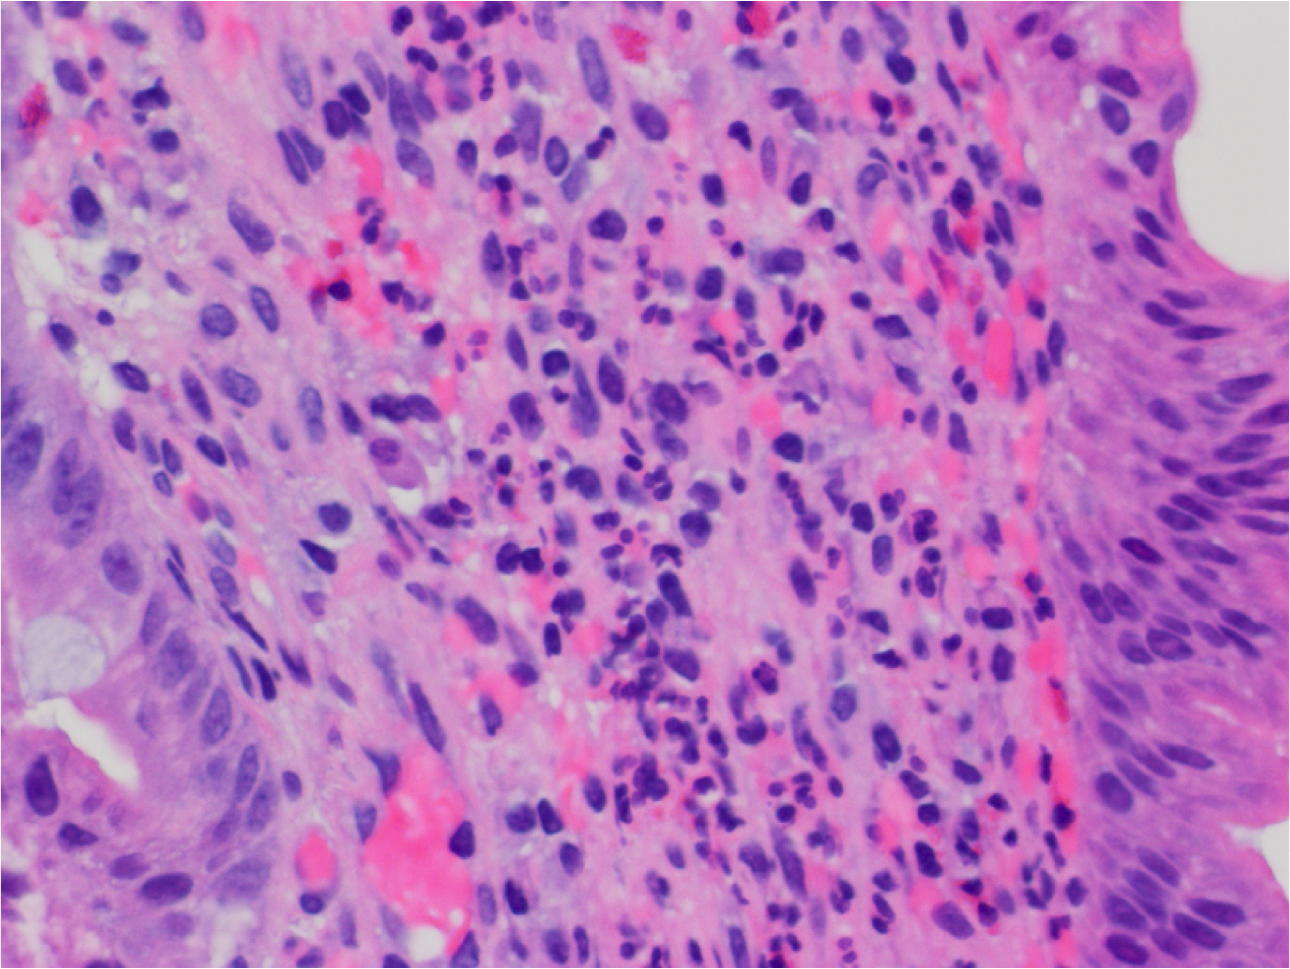

What’s this?

H Pylori infection

High power view showing lymphocytes, plasma cells and admixture of eosinophils. Presence of neutrophils (small segmented nuclei in the upper left) indicates active inflammation which is very characteristic of H pylori infection.